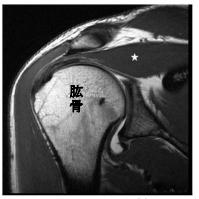

29 附圖為肩部核磁共振的冠狀斜向(coronal oblique)某一切面影像,其中以白色星狀標示的結構為何?

(A)三角肌(deltoid) (B)棘上肌(supraspinatus) (C)小圓肌(teres minor) (D)大圓肌(teres major)